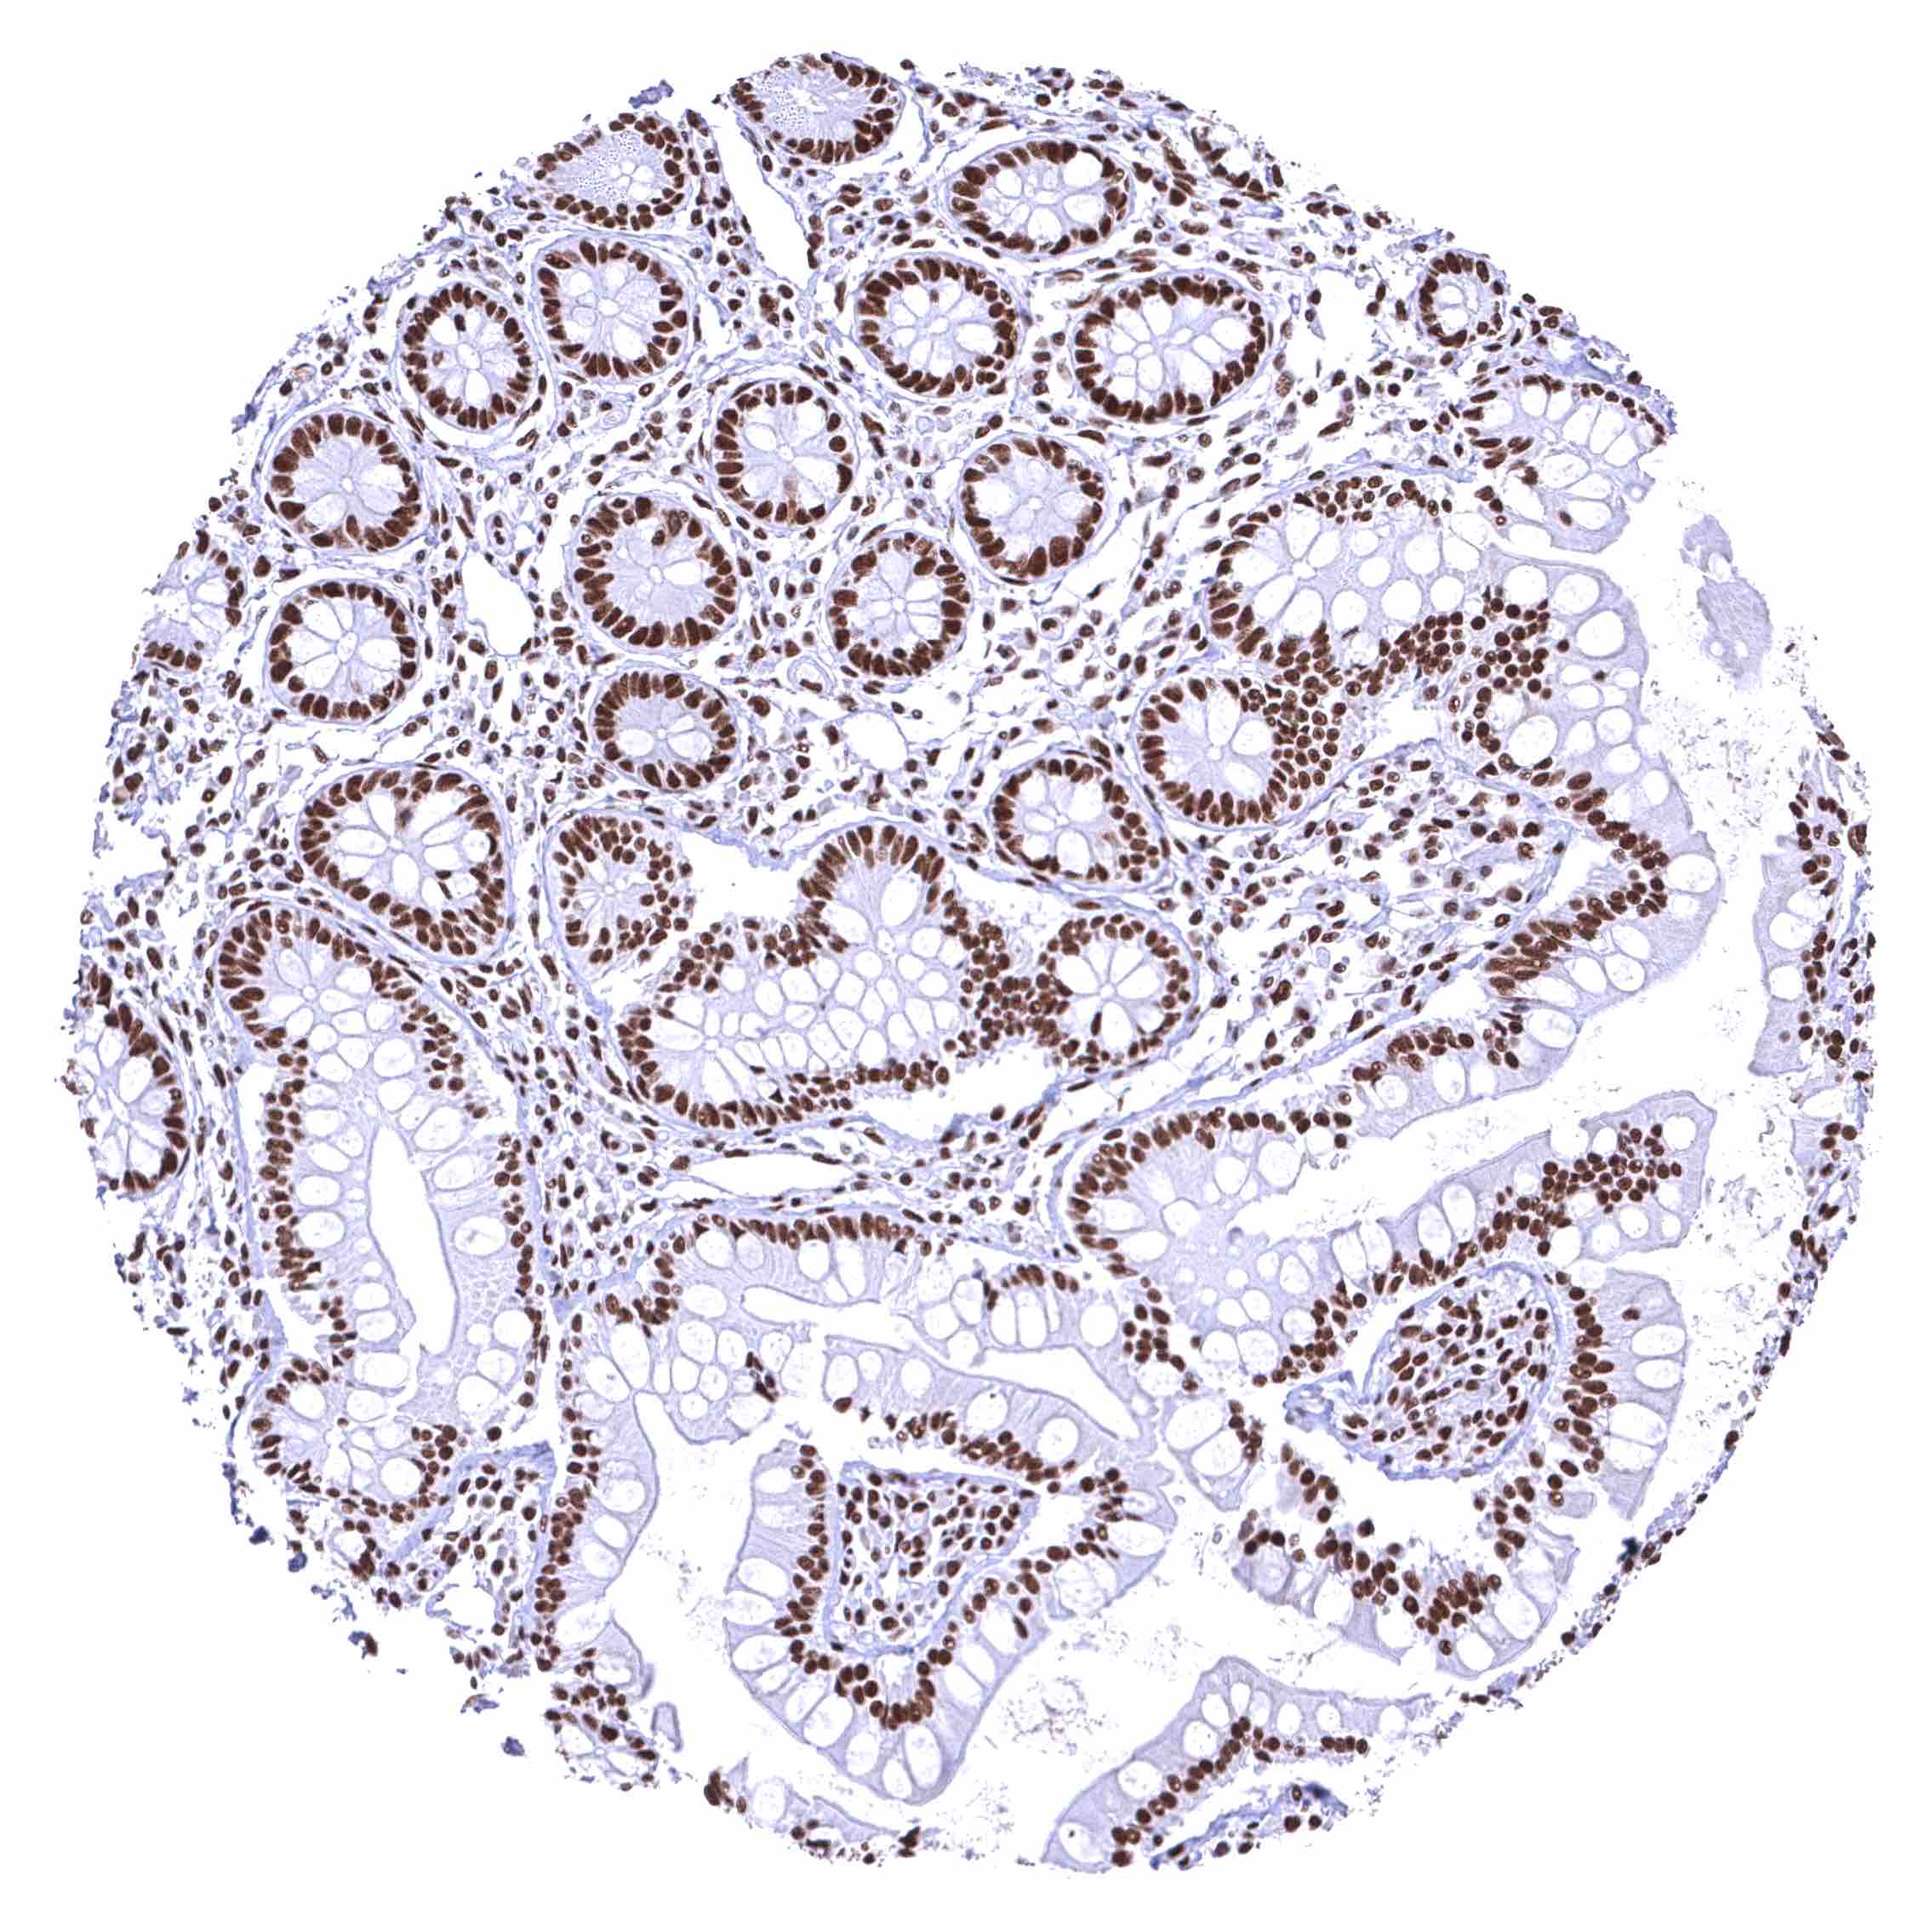

Colon descendens, mucosa – Nuclear BRD4 staining of surface epithelial cells is weaker than in crypts.

Rectum, mucosa – Nuclear BRD4 staining of surface epithelial cells is weaker than in crypts.